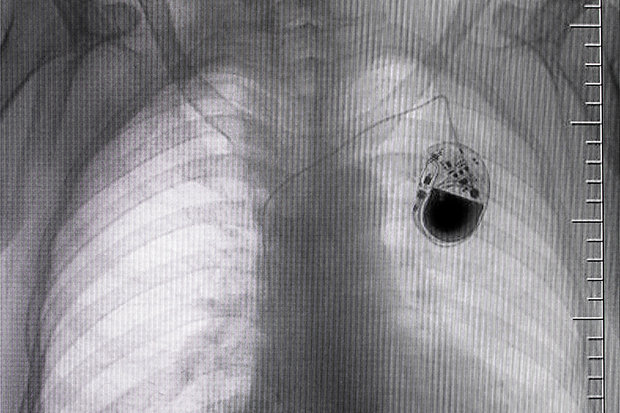

This issue was highlighted last week when the FDA issued a letter calling for the voluntary recall of some 465,000 St. Jude Medical pacemakers—currently embedded in heart patients’ chests!—to patch security holes.

The FDA warned that vulnerabilities in the RF-enabled implantable cardiac pacemakers “if exploited, could allow an unauthorized user … to access a patient’s device using commercially available equipment. This access could be used to modify programming commands to the implanted pacemaker, which could result in patient harm from rapid battery depletion or administration of inappropriate pacing.”

In other words, hackers might be able to run down the battery so the device would prematurely stop working, or they could even affect the patients’ heart rate or rhythm.

Fortunately, according to Abbott, which now owns St. Jude Medical, no compromised pacemakers have yet been reported. And in the vast majority of cases, the vulnerable firmware can be updated with a simple, three-minute visit to a healthcare provider.